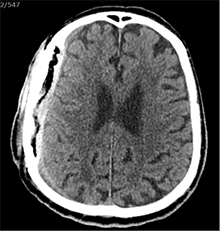

53 m. vyras sumuštas gatvėje ir greitosios medicinos pagalbos atvežtas į Priėmimo skyrių. Pacientui atlikta galvos kompiuterinė tomografija (GKT). Rasta: poūmė, stora, apie 16 mm dydžio subdurinė hematoma (SDH) dešinėje pusėje konveksitaliai ir ūmi nedidelė SDH kairėje pusėje frontoparietaliai. Vidurio struktūrų dislokacija (VSD) į kairę – minimali. Kairėje – kaukolės skliauto linijinis lūžis. Nustatyta nosies kaulų, nosies pertvaros, dešiniojo viršutinio žandikaulio kaktinės ataugos ir kūno, sinuso sienelių lūžių, dešinės akiduobės medialinio krašto lūžių ir dešiniojo skruostinio lanko lūžių (1 pav.). 2020 m. liepos mėn. pacientas skubos tvarka operuotas: atlikta dešinė kraniotomija, pašalinta hematoma. Atlikus kontrolinę GKT, buvo matyti, kad pašalinta didžioji hematomos dalis (2 pav.). Pacientas konsultuotas veido ir žandikaulio chirurgo, skubus chirurginis gydymas neindikuotas. Praėjus 3 savaitėms, pacientas, esant gerai funkcinei ir neurologinei būklei, tolesnio gydymo perkeltas į slaugos ligoninę, vėliau išleistas gydytis ambulatoriškai.

2 pav. Po pirmosios operacijos (didžioji hematomos dalis pašalinta, VSD be dislokacijos)